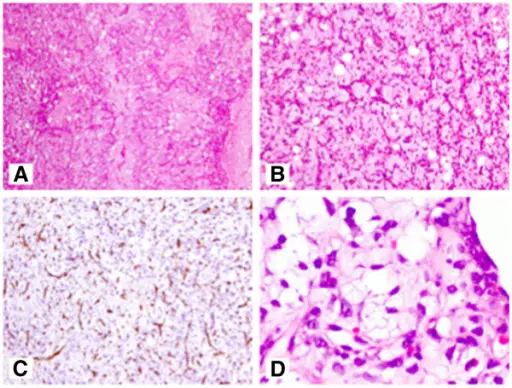

Rhabdomyosarcomas are malignant tumors composed mainly of skeletal muscle.

Diagnosis is made by histology showing malignant skeletal muscle with rhabdomyoblasts, which are the characteristic cells of rhabdomyosarcoma.

Pathology stains for rhabdomyosarcoma will be desmin stain positive.